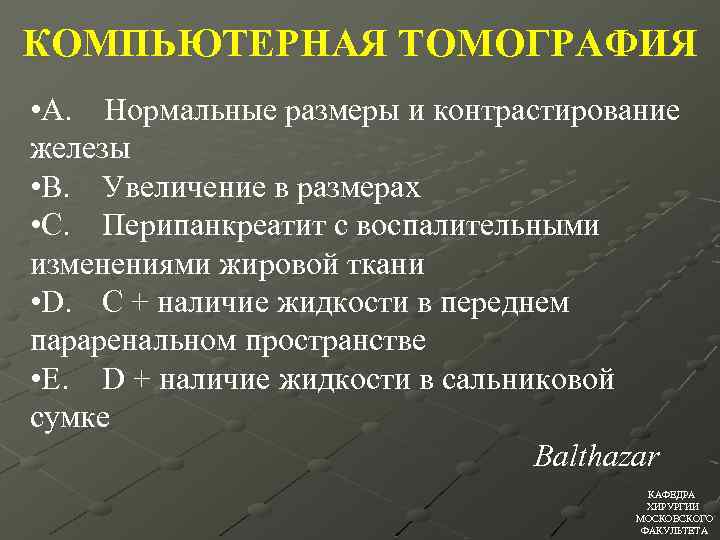

КОМПЬЮТЕРНАЯ ТОМОГРАФИЯ • А. Нормальные размеры и контрастирование железы • B. Увеличение в размерах • C. Перипанкреатит с воспалительными изменениями жировой ткани • D. С + наличие жидкости в переднем параренальном пространстве • E. D + наличие жидкости в сальниковой сумке Balthazar КАФЕДРА ХИРУРГИИ МОСКОВСКОГО ФАКУЛЬТЕТА

КОМПЬЮТЕРНАЯ ТОМОГРАФИЯ • А. Нормальные размеры и контрастирование железы • B. Увеличение в размерах • C. Перипанкреатит с воспалительными изменениями жировой ткани • D. С + наличие жидкости в переднем параренальном пространстве • E. D + наличие жидкости в сальниковой сумке Balthazar КАФЕДРА ХИРУРГИИ МОСКОВСКОГО ФАКУЛЬТЕТА